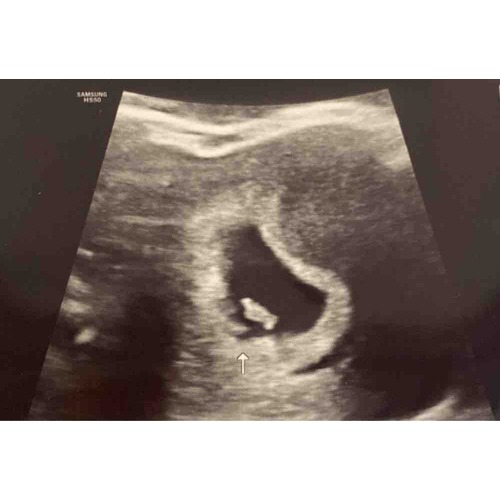

Hoi allen, hoe is het uiteindelijk bij jullie allemaal verlopen? Wij hadden gister onze eerste echo (ongeveer 6.3 wk) en onze Vk was ook wat voorzichtig met goed nieuws brengen door de vorm van de vruchtzak. Echter wel een hartslag; langzaam maar dit hoeft nog niets te betekenen met dit termijn.

Ik heb tijdens bloedverlies twee echo's gehad met een kloppend hartje. Veel stolsels ook om de vruchtzak heen in mijn baarmoeder.

Vier dagen later op de echo geen kloppend hartje meer en de vk zei toen nog dat de vruchtzak er ook niet mooi rond meer uit zag. Dus bij mij was dat helaas geen goed teken.